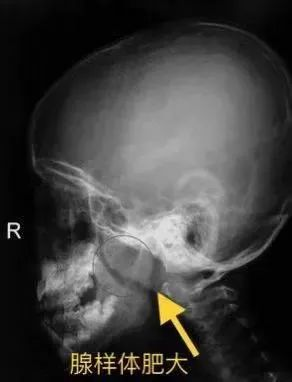

4、鼻咽部X线侧位片和CT检查。观察鼻咽部软组织是否出现增厚。1、有典型“腺样体面容”者,诊断较容易。口咽部常见黏脓液从鼻咽部流下,常见腭扁桃体肥大。2、鼻咽镜检查。若腺样体较大,可将鼻咽部全部占满并阻塞后鼻孔。3、鼻咽侧位拍片及CT、MR扫描可判断腺样体的部位及大小,如果腺样体组织占到通气道的70%以上,即可诊断为腺样体肥大。